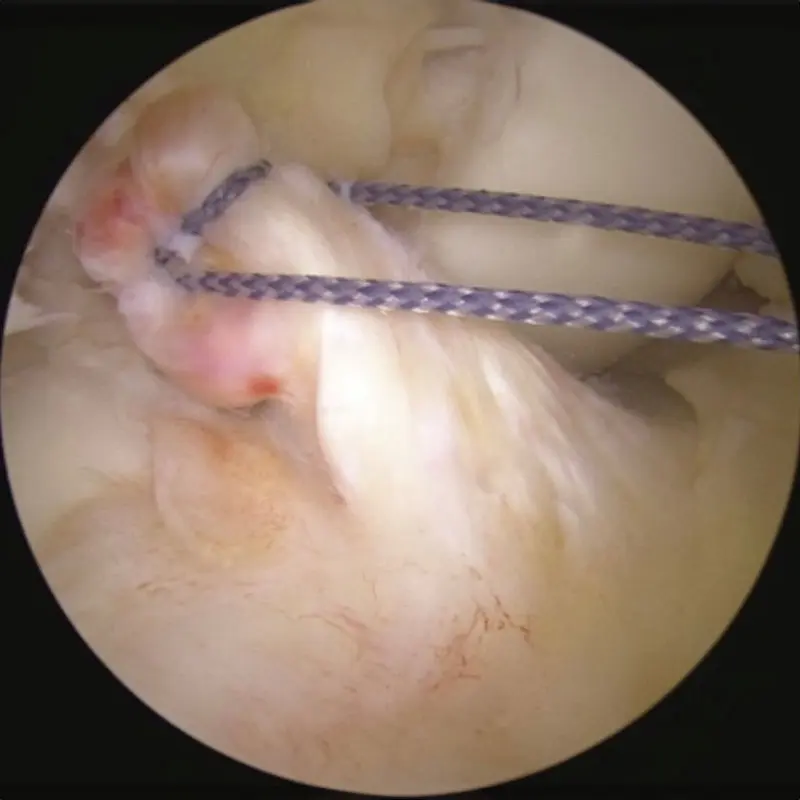

View of ACL stump being pulled into position before placement of BEAR implant.